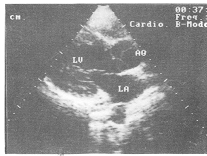

3. 主动脉瓣四叶畸形: 左室长轴观见主动脉瓣关闭呈“”形, 大血管短轴观呈“十”字形。 相邻半月瓣间见四处主动脉附着点, 开放时半月瓣向四个方向运动, 接近主动脉壁, 可清楚地显示大小不等的四个半月瓣, (图1,2)。

图2 大血管短轴切面显示主动脉瓣四叶畸形呈“+”形